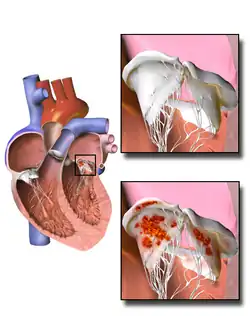

Damaged valves and endocardium contribute to the development of infective endocarditis.[38] Specifically, the damaged part of a heart valve forms a local blood clot, a condition known as non-bacterial thrombotic endocarditis (NBTE). The platelet and fibrin deposits that form as part of the blood clotting process allow bacteria to take hold and form vegetations. As previously mentioned, the body has no direct methods of combating valvular vegetations because the valves do not have a dedicated blood supply. This combination of damaged valves, bacterial growth, and lack of a strong immune response results in infective endocarditis.